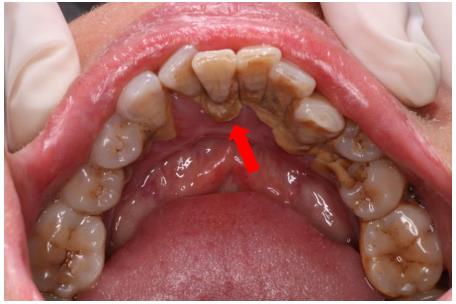

2.牙結(jié)石

臨床表現(xiàn)變化: